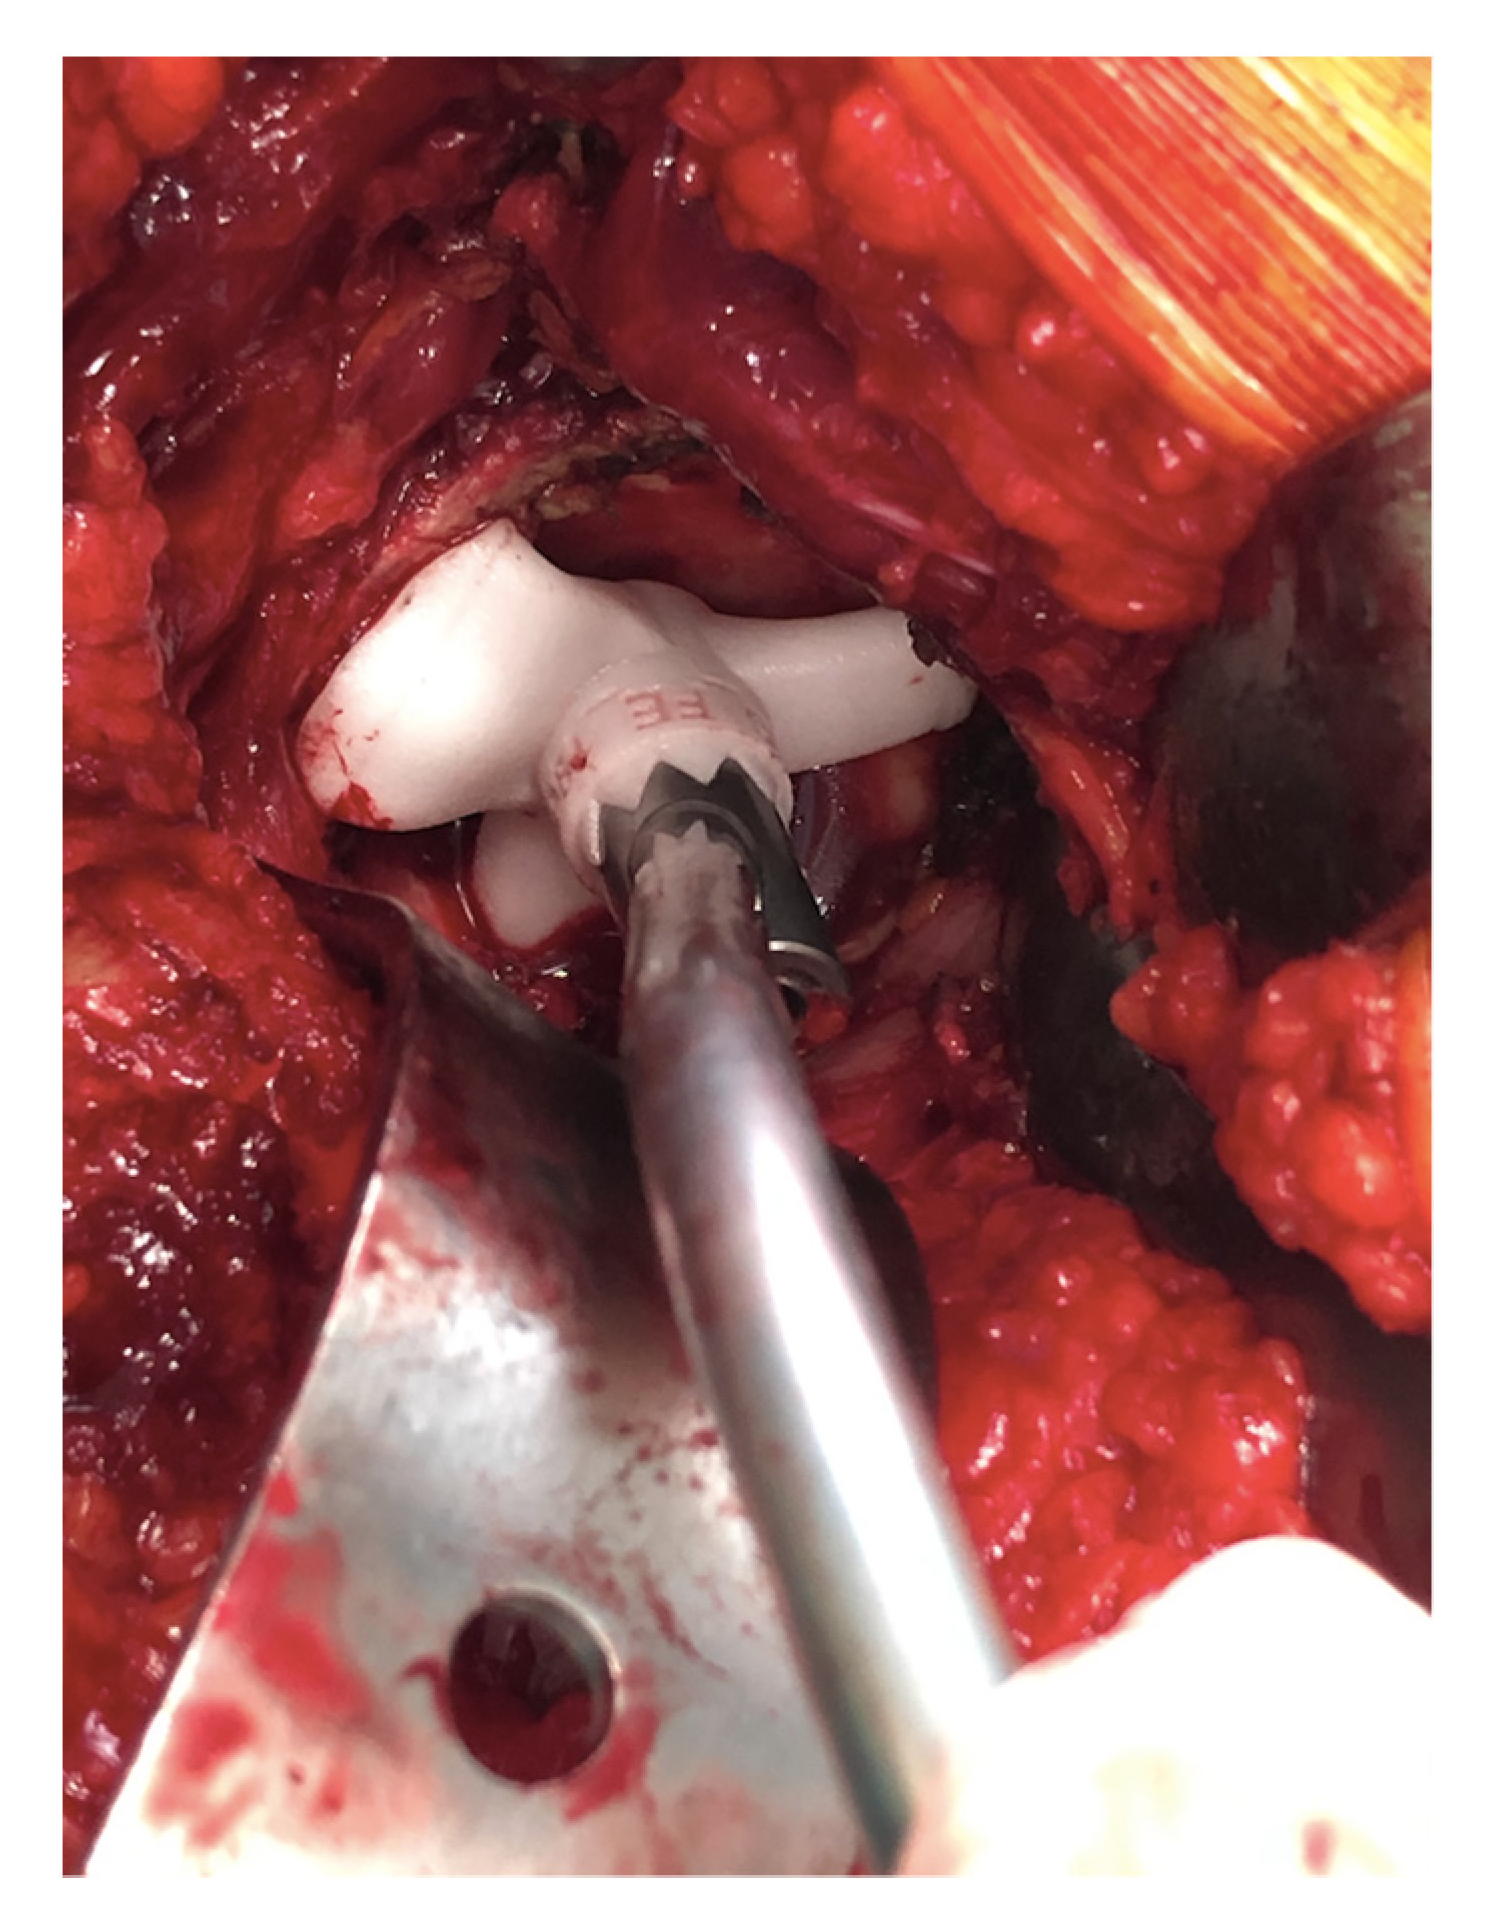

2.1. Surgical Technique